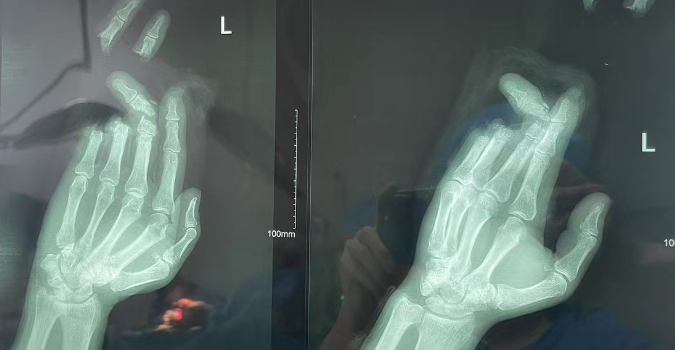

王女士,28岁,因遗传+长期穿高跟鞋导致踇外翻,外翻角度超40°,伴有疼痛和行走困难。她因工作需要,希望尽快手术。李龙飞医生评估后,决定采用微创手术,并制定详细术前准备和术后康复计划。手术顺利,王女士恢复良好,工作前已能正常行走,疼痛减轻。她感激地说:“李医生不仅治愈了我的脚,更让我在重要时刻能够自信地站出来。”